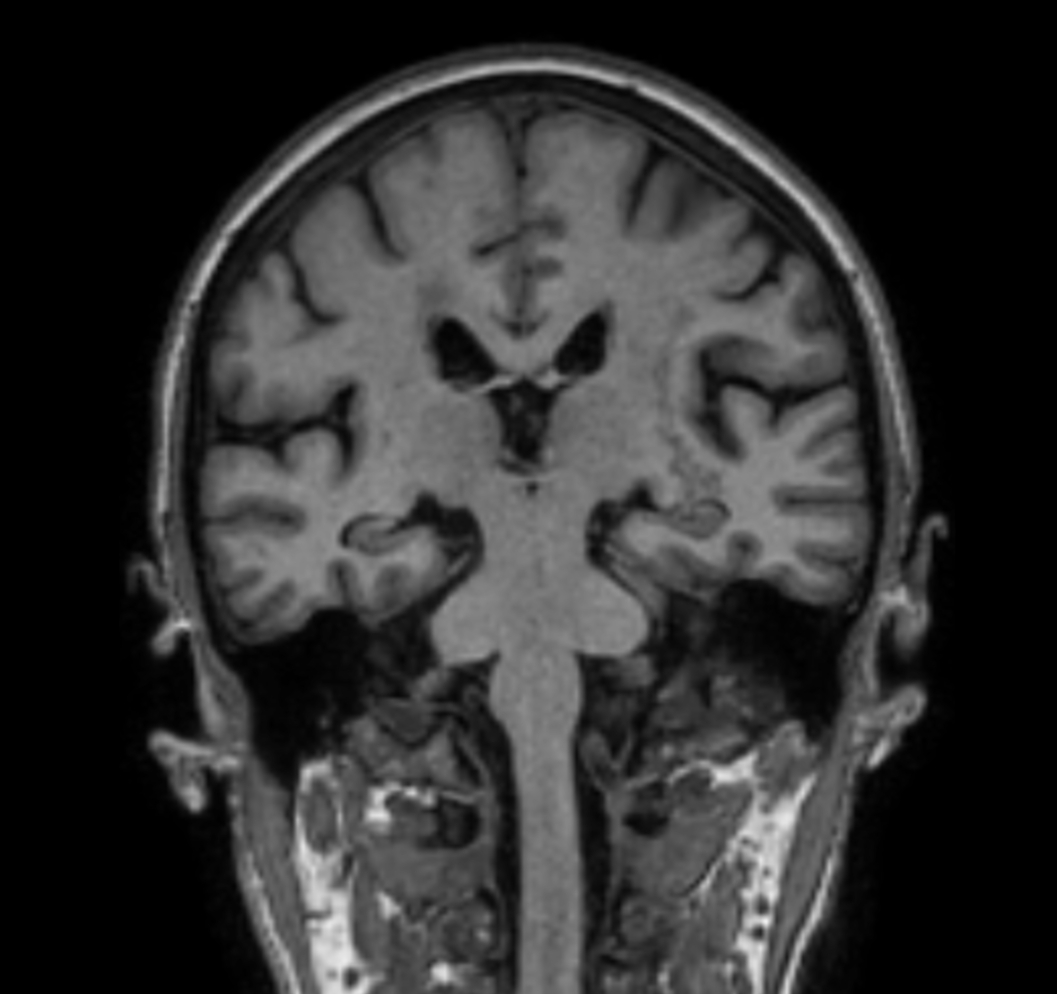

3D VIEW - T1w TFE (coronal reformat)